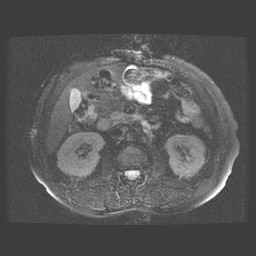

Bekken